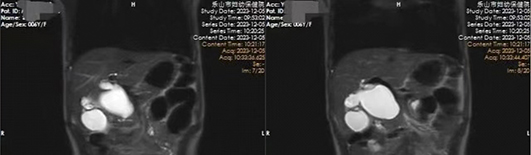

芯芯(化名)于2023年12月5日凌晨因“腹痛伴嘔吐3天”急診收入我院小兒外科。醫(yī)生仔細(xì)詢問病史、查體并結(jié)合輔助檢查結(jié)果,診斷為先天性膽總管囊腫。經(jīng)與家屬充分溝通,完善各項(xiàng)術(shù)前準(zhǔn)備后,由院長包平倩帶領(lǐng)小兒外科團(tuán)隊(duì)成功為患兒實(shí)施腹腔鏡下先天性膽總管囊腫切除膽道成形術(shù)。

據(jù)了解,患兒術(shù)中膽總管呈現(xiàn)囊性擴(kuò)張,最大直徑約5cm,且囊性擴(kuò)張部分與腸管及周圍組織粘連緊密,極大地增加了手術(shù)難度。小兒外科手術(shù)團(tuán)隊(duì)?wèi){借著精湛的技藝完成剝離,切除囊腫,順利完成手術(shù)。術(shù)后在醫(yī)護(hù)團(tuán)隊(duì)的精心照護(hù)下,患兒恢復(fù)良好,目前已康復(fù)出院。

先天性膽總管囊腫也被稱為先天性膽管擴(kuò)張癥,是小兒常見的一種先天性膽道疾病,在亞洲東方人中的發(fā)病率明顯高于歐美白人,女性發(fā)病高于男性,占總發(fā)病率的60%~80%。其病變主要是指膽總管的一部分呈囊狀或梭狀擴(kuò)張,有時(shí)可伴有肝內(nèi)膽管擴(kuò)張的一種先天性畸形。以腹痛、腹部腫塊、黃疸為主要臨床表現(xiàn),本病一經(jīng)診斷均需及早手術(shù),以解除癥狀、避免梗阻性黃疸導(dǎo)致的膽汁性肝硬化、癌變穿孔等嚴(yán)重并發(fā)癥。此疾病術(shù)前可以通過腹部超聲、CT、MRCP來進(jìn)行輔助診斷。腹腔鏡手術(shù)具有創(chuàng)傷小、出血少、恢復(fù)快等優(yōu)點(diǎn),也縮短了住院時(shí)間,目前已被廣泛應(yīng)用于先天性膽總管囊腫的治療。據(jù)悉,西南地區(qū)地市級婦幼專科醫(yī)院能獨(dú)立開展此類手術(shù)的機(jī)構(gòu)屈指可數(shù),隨著我院小兒外科的成立,成功開展此類手術(shù),填補(bǔ)了樂山地區(qū)婦幼專科醫(yī)院治療此類疾病的技術(shù)空白。